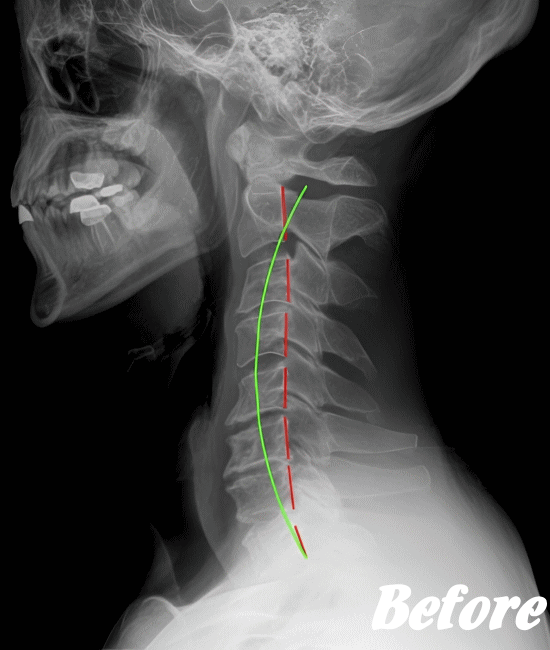

頚椎を斜め後方へ反らせると上肢に放散痛が現れたり、首の可動域、感覚異常があるかどうか…等々を確認した上で、レントゲンやCT、MRIなどによる画像検査を行います。

HALOカイロプラクティック☆平和島整体院では、骨盤から背骨全体を調整し、首(頚椎)の詰まりを一つ一つ広げ、肩甲骨の可動を柔軟にし、首周りの筋肉をゆるめることで、首の負担が解消され、痛みや痺れを改善していきます。

手術を要するヘルニアでない限り、多くの人は回復しています。